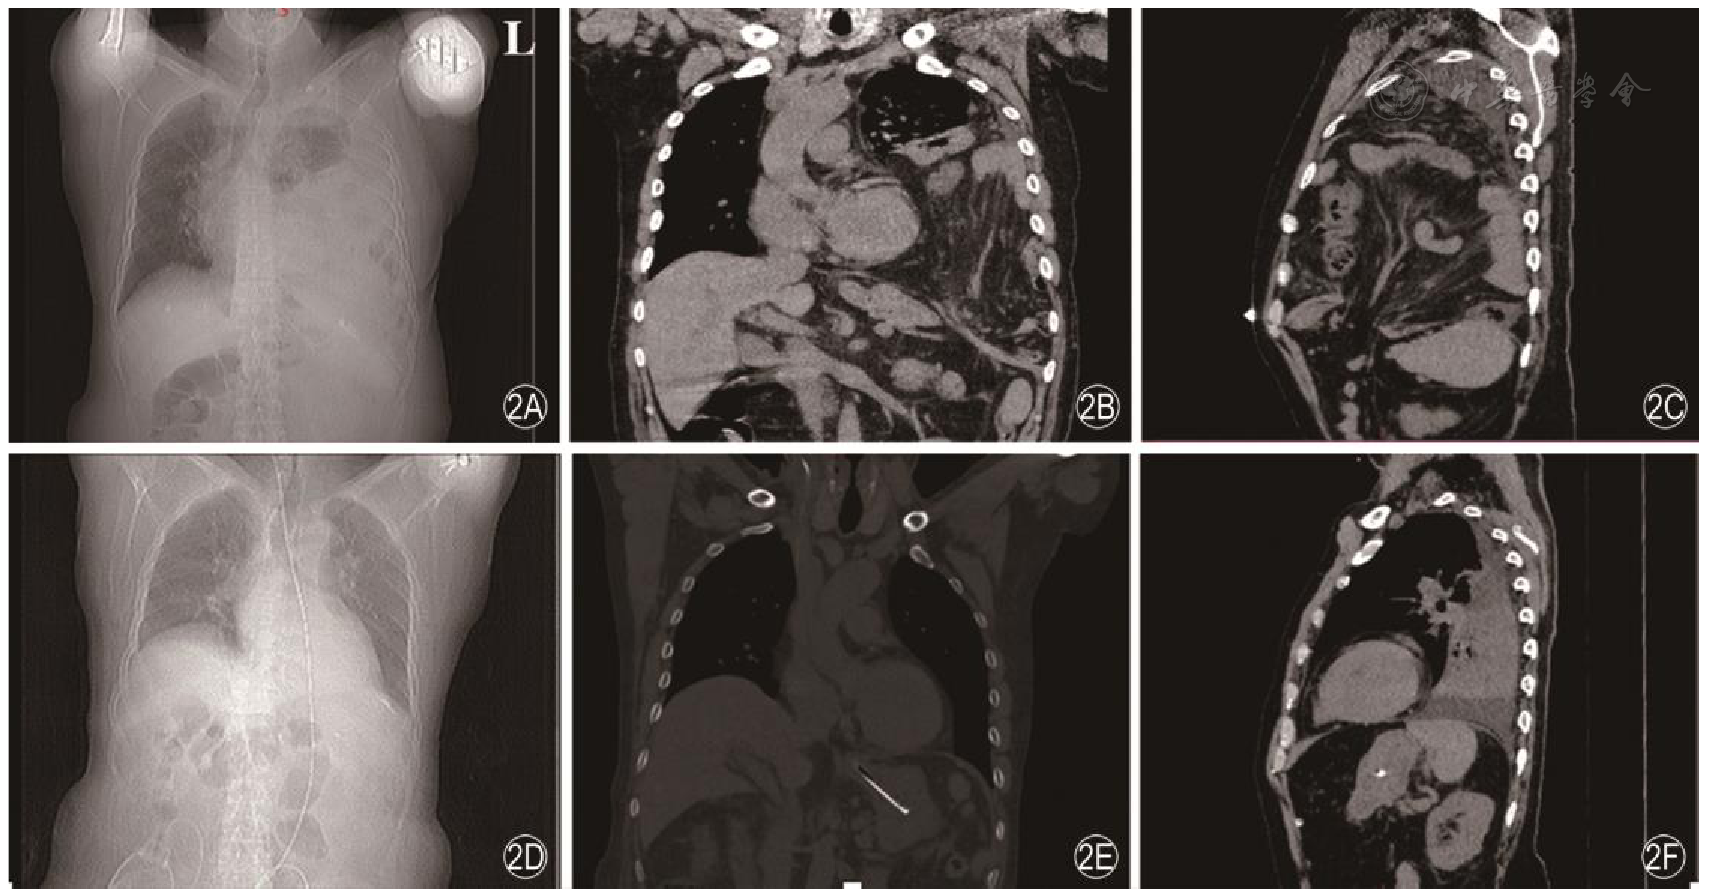

翁山耕, 陈易平, 张翔. 成人膈疝的诊治策略[J]. 中华普通外科杂志, 2025, 40(9): 677-682.